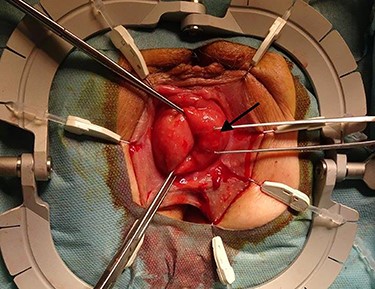

The surgical site was adjusted using a Lonestar retractor and the prolapse was exposed further using Allis clamps (Fig. 2). A monopolar current incision was made slightly above the dentate line, followed by circular dissection of the rectum starting from the ventral aspect (Fig. 3). The entire tumor area between three and six in lithotomy position (3 cm in diameter) was completely reduced (Fig. 4). No penetration was visible on the serosa side. The prolapse was then shortened and a tension-free coloanal anastomosis was created using several Monocryl 4.0 sutures.

Completely resected tumor of rectum, 3.6-cm long and up to 3.0 cm in diameter. (a) Front view. (b) lateral view.